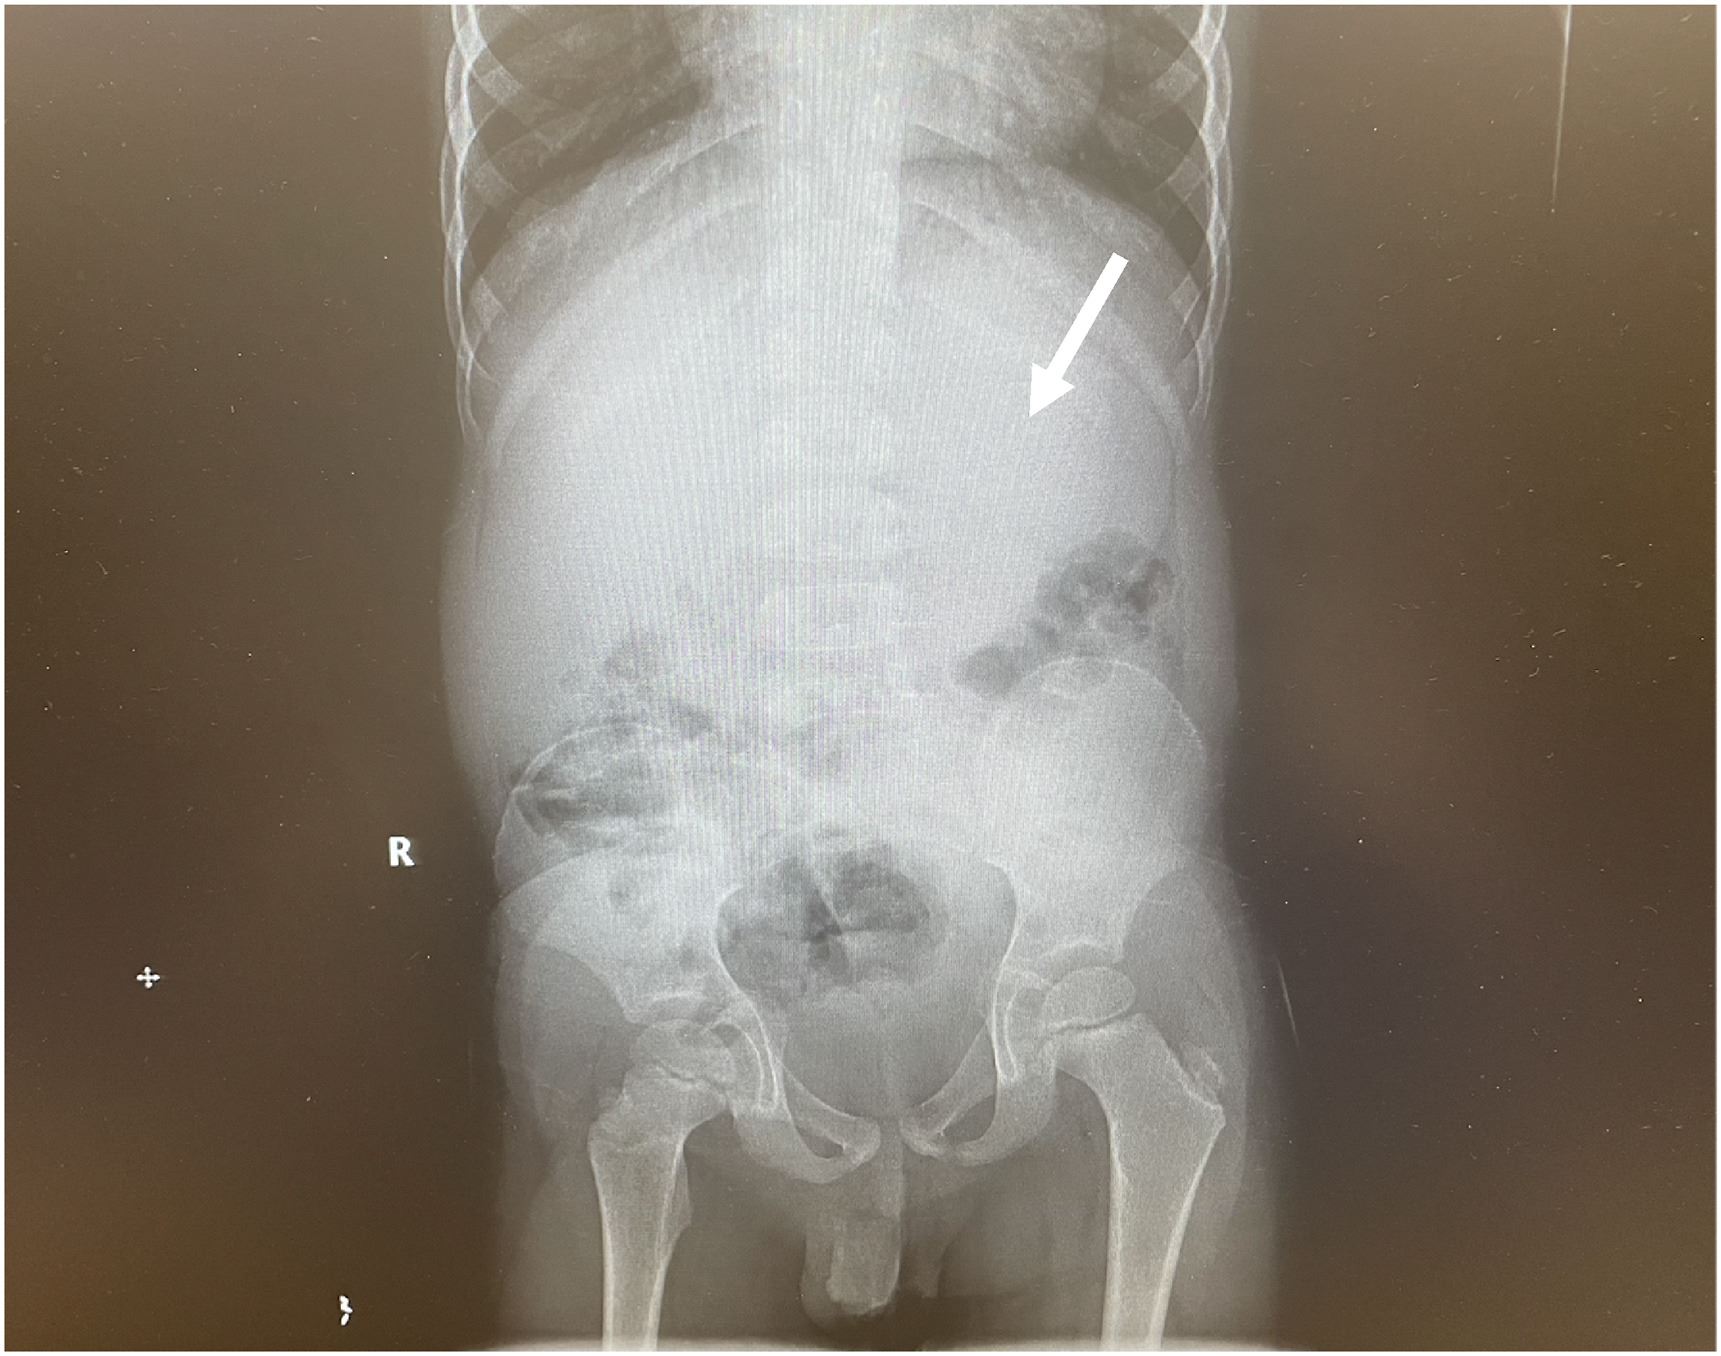

Ekoran itu, pasukan doktor yang diketuai oleh Dr. Chizite Iheonunekwu di Klinik Cleveland mula melakukan prosedur pembedahan dan menarik keluar gumpalan gula-gula menerusi kerongkong beliau.

Jelas doktor, gumpalan gula-gula yang disebut sebagai bezoar tersekat pada perut kanak-akanak ini hingga mengambil kira-kira 25 peratus ruang.

Dengan menggunakan skop khas, doktor kemudian mengeluarkan gumpalan berkenaan melalui esofagus atau kerongkong. Prosedur itu terpaksa dilakukan berulang kali bagi mengeluarkan kesemua gula-gula getah yang tersumbat.